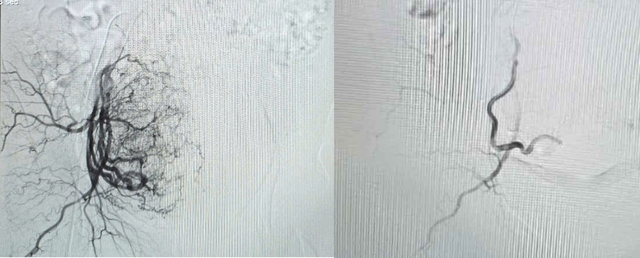

Hình ảnh tăng sinh mạch máu tử cung trước và sau can thiệp

Sau đó, ê-kíp can thiệp thủ thuật nút mạch tử cung bằng keo sinh học và sau khi xác định vị trí chảy máu, ê-kíp tiến hành tắc mạch thành công sau 45 phút. Ngay sau khi kiểm soát tình trạng chảy máu, bệnh nhân được sử dụng ngay kháng đông để điều trị thuyên tắc phổi. Hiện sức khoẻ bệnh nhân ổn định, không còn tình trạng xuất huyết, sinh tồn ổn định, tiếp tục điều trị kháng đông theo phác đồ thuyên tắc phổi.